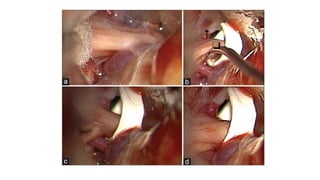

Microvascular Decompression

• JANNETTA PROCEDURE

• Most effective surgical

procedure

• Addresses the etiology directly

• Younger, healthier patients

• Retro-sigmoid craniotomy

Microvascular Decompression • JANNETTAPROCEDURE • Most effective surgical procedure • Addresses the etiology directly • Younger, healthier patients • Retro-sigmoid craniotomy

• #18 Also known as the Jannetta procedure. Peter Janetta was a neurosurgery registrar that first proposed the neurovascular compression theory. He built upon the astute observations of Dandy, Gardner, and others who, in the era before the operating microscope, had successfully ventured into the posterior fossa. Usually indicated for younger, healthier patients that are good surgical candidates. MVD involves exposing the trigeminal nerve at the base of the skull, typically via a craniotomy, and inserting Teflon pads between the artery thought to be compressing the nerve. The chief advantage of this technique is that the pain relief is typically durable and likely curative. Not surprisingly, the use of MVD increased by 194% from 1988 to 2008. However, while MVD remains the treatment of choice for trigeminal neuralgia, it is also the most invasive procedure with the highest rate of complications.